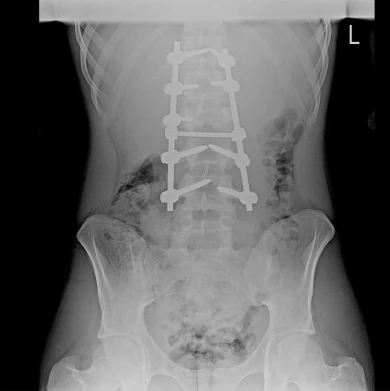

Проблемы и достижения воронежской медицины